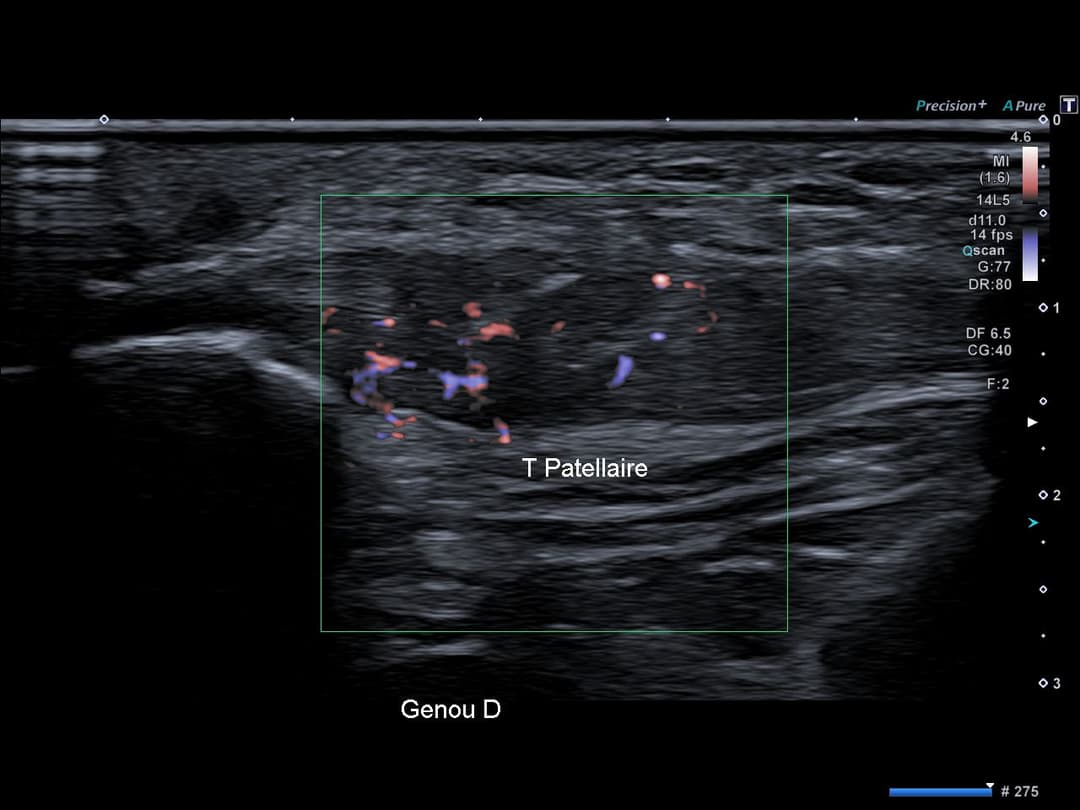

Franche néovascularisation globale du tendon en Doppler couleur.